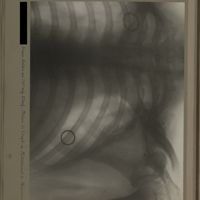

0126 - Page 14 - [Radiographie du thorax]0126 - Page 14 - [Radiographie du thorax]

0179 - Page 67 - [Radiographies du thorax]0179 - Page 67 - [Radiographies du thorax]

0210 - Page 98 - [Radiographies du thorax]0210 - Page 98 - [Radiographies du thorax]